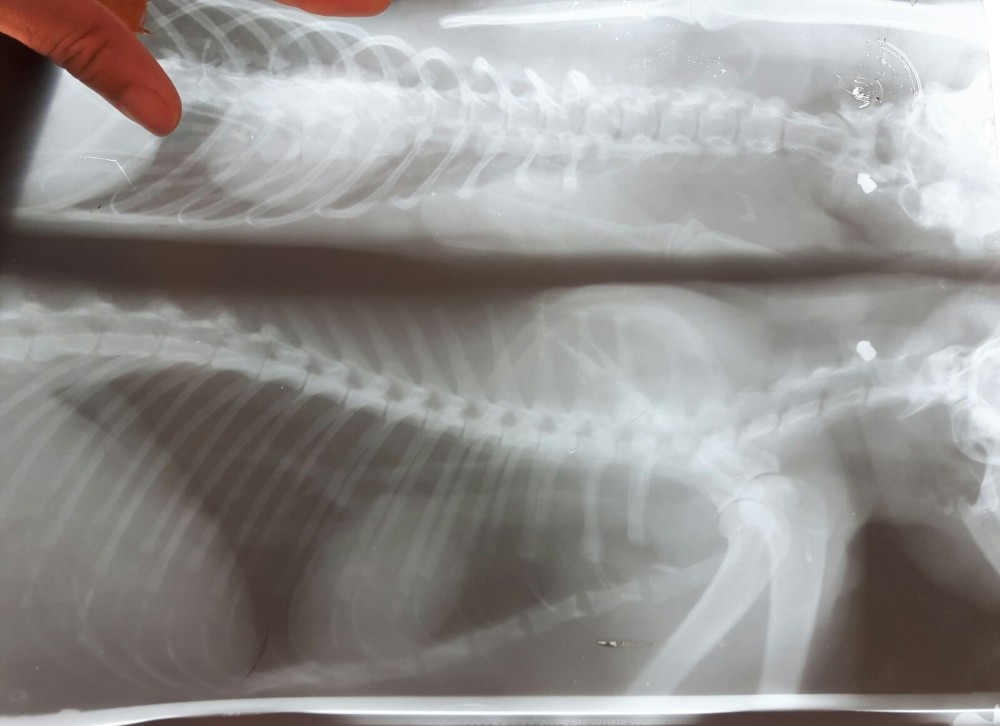

Edinilen bilgiye göre, Konyaaltı ilçesi Hurma Mahallesi 224 Sokak’ta dün gece bir kedi, kimliği belirlenemeyen kişi ya da kişilerce havalı tüfekle ateş edilmesi sonucu yaralandı. Sabah besleme noktasına gelen hayvanseverler bir kedinin hareketsiz şekilde yattığını görünce Büyükşehir Belediyesi Hayvan Bakımevine götürdü. Kedinin, boyun kısmına bir saçma isabet ettiği belirlendi.

Kedilere yüksek bir yerden havalı tüfekle ateş edildiğini dile getiren Gürsel, “Diğer olaylarda polis merkezine şikayete gittik. Ama ateşli silah olmadığı için balistik incelemesi yapılamadı. Bu kedimizin röntgeninde boynunda bir saçma tespit edildi. Şuan tedavisine devam ediliyor. Tekrar polis merkezine ve savcılığa şikayette bulunacağız. Bu şüpheliyi yakalamadıkça olayların arkası kesilmeyecek. Saçmalardan birisi o bölgede oynayan insanlara da gelebilir. Bir canımızın daha saçmaların hedefi olmaması için konunun sonuna kadar takipçisi olacağız” dedi.